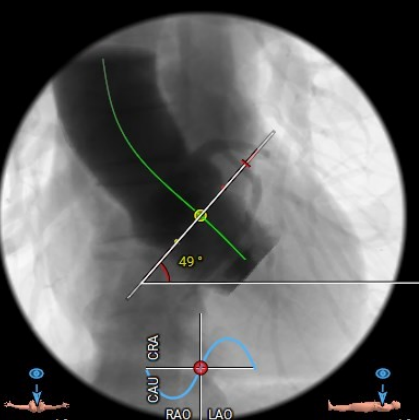

心脏角度:

49°

● 主动脉根部:患者主动脉瓣为三叶瓣,左右冠窦可见部分粘连,重度钙化,瓣环到LVOT层面可见钙化,法式窦结构较大,左冠开口高度约11.0mm,右冠开口高度约16.2mm,STJ高度约19.5mm,直径约28.1mm,升主动脉未见明显扩张,心脏角度约49°,左室形态稍小,心肌增厚。